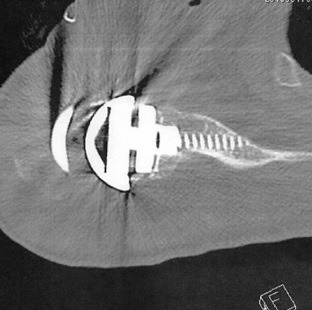

術後画像

術直後Xp

術後CT